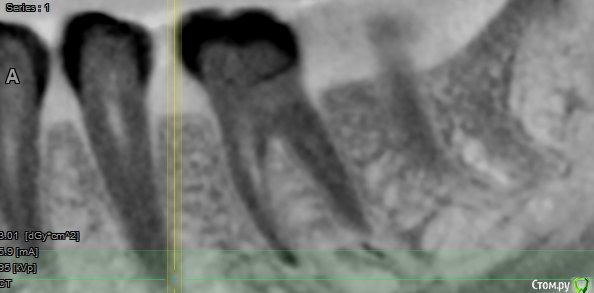

В общем, сходила я в другую клинику, сделали рентген, посмотрели, выписали антибиотики, дали месяц зубу, коронку на него нельзя, и по их словам даже если выживет, то около года протянет. На сегодняшний день, изменения не особо: в определенном смыкании боль осталась, бывает даже от прикосновения к зубу, не сильная, либо я за полгода лечения привыкла к ней. На днях сделала 3д снимок, хотелось бы узнать мнение профи: делать имплант, одноэтапный? надо наращивать кость? или всё же ещё раз перелечить зуб?

post-57643-0-51490300-1555936940_thumb.png